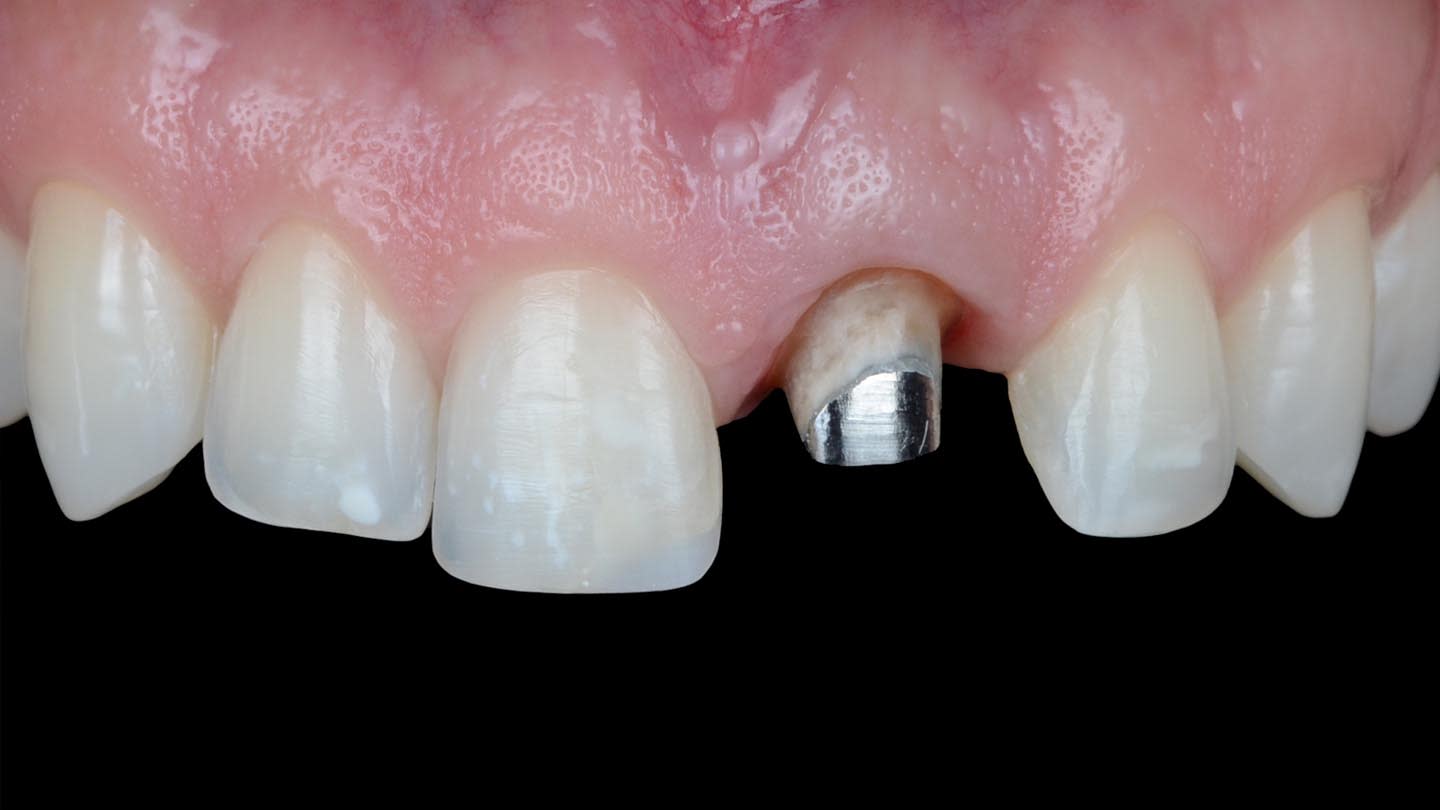

A 40-year-old male patient presented to the author’s (MR) office with the request to improve the esthetics of his smile, as there were several extensive infiltrated composite restorations and a chipped crown showing a severe dark color on an endodontically treated tooth (Figure 1 and Figure 2).

Following a comprehensive clinical, radiographic, and initial photographic assessment, ceramic restorations were chosen to restore function and esthetics. Given that the underlying structure of tooth No. 9 was presented with a fractured crown, a metal cast post, and dark discoloration, it was decided to fabricate a crown with an opaque core using high-opacity LDS ceramic along with a bonded lithium-disilicate veneer on top to enhance the esthetic outcome. For teeth Nos. 7, 8, and 10, LDS ceramic veneers were chosen.